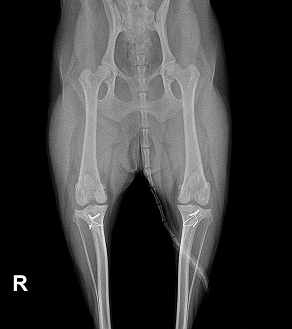

BEFORE

AFTER